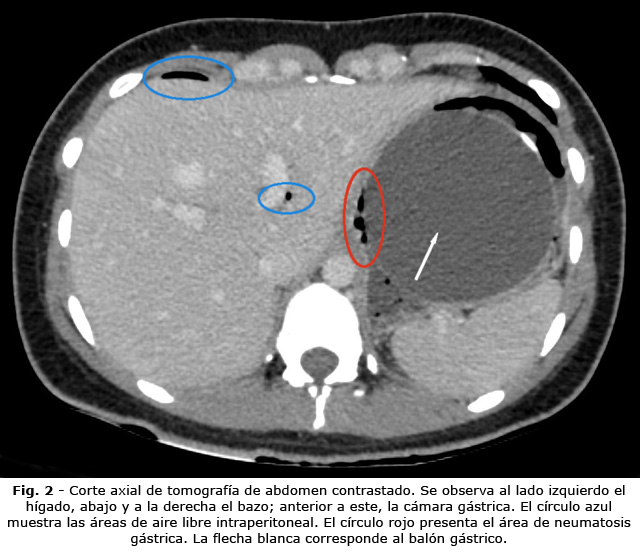

Ante la sospecha de posible perforación secundaria, se decidió solicitar radiografía toracoabdominal de pie, para evaluar la presencia de neumoperitoneo. Se realizó radiografía del tórax en la cual se evidenció neumoperitoneo subdiafragmático derecho reducido (Fig. 1). Se procedió a realizar tomografía axial computarizada (TAC) contrastada de abdomen, que reportó signos que sugerían perforación gástrica (engrosamiento de las paredes del estómago, asociado a neumatosis de la pared y aire libre intraperitoneal) (Fig. 2 y Fig. 3), asociados a cambios inflamatorios intraperitoneales.